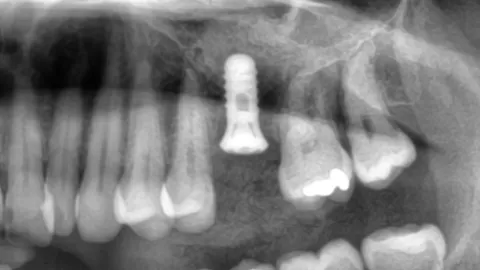

I bloggen hittar du artiklar om de senaste framstegen inom tandimplantat, inklusive tekniker som möjliggör direktinstallation av implantat i samband med tandutdragning, användning av tillväxtfaktorer som PRF och PRP för snabbare läkning samt hur modern bilddiagnostik och kirurgiska guider bidrar till ökad precision och kortare behandlingstid. Vi berättar också om hur vi arbetar med avancerade lösningar som benaugmentation, sinuslyft och UV-aktivering av implantatytor med Plasmaprep™ för att optimera resultatet.

Sinuslyft – Bygg upp ben för tandimplantat i överkäken Har du för lite ben för...

Läs hur vi med hjälp av sinuslyft och benmaterial kunde möjliggöra stabil implantatbehandling i överkäken...